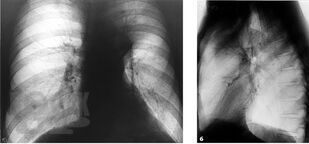

Учебное пособие основано на современных данных по диагностике и лечению рака легкого. Оно содержит информацию об эпидемиологии, этиологии, клинических проявлениях и профилактике заболевания.

В издании изложены сведения о современных методах исследования, применяемых для диагностики, оценки стадии заболевания с учетом Международной классификации по системе TNM и выбора оптимального метода лечения.